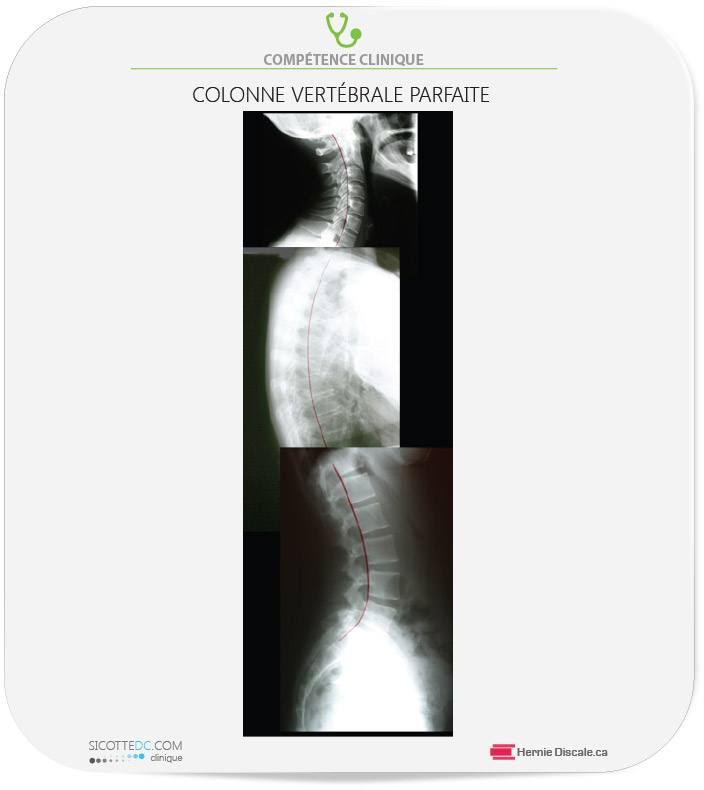

LA COLONNE VERTÉBRALE PARFAITE

Une colonne vertébrale saine affiche des courbes qui lui permettent de conserver sa santé et de préserver le fonctionnement du système nerveux. Une colonne dépourvue de courbures est une colonne faible. Le cou et le bas du dos doivent avoir une courbure vers l’avant, et le milieu du dos doit avoir une légère courbure vers l’arrière.